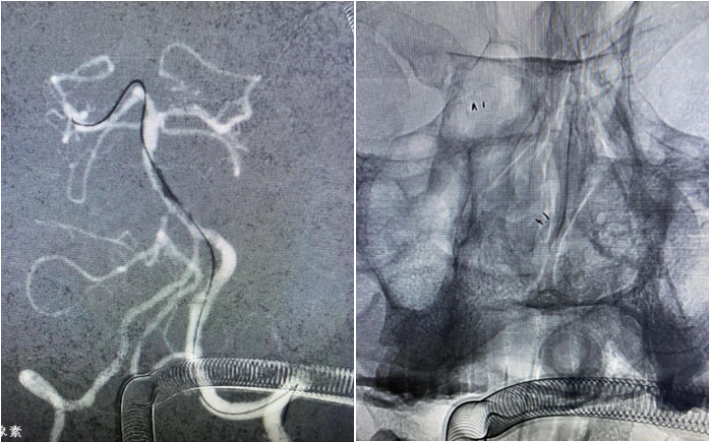

南阳市中心医院神经内科脑血管病介入团队紧急支援救场拍马赶到。手术方案考虑1.球囊扩张,支架里面还有血栓,行球囊扩张可能血流难以维持。2.球囊扩张支架植入,再次植入支架,但原支架➕血栓作为异物,难免再次血栓。3.取出支架及血栓。

取出支架及血栓,可能的后果,1.取栓支架无法套住原支架,无法再通;2.取栓支架套住原支架但无法取出体外,不得已在颅内解脱取栓支架;3.支架牵拉过度导致血管破裂出血。如果出现第二种情况,只能用Solitaire AB,别的取栓支架无法解脱,将进退两难。

经过尝试,支架导管Rebar 18➕Synchro导丝200cm通过变形严重的原支架Enterprise 2。

打开取栓支架。

Solitaire AB 4mmx20mm成功挂住Enterprise 2。

尝试回收支架至5F Navien,牵扯力量比较大,提心吊胆。